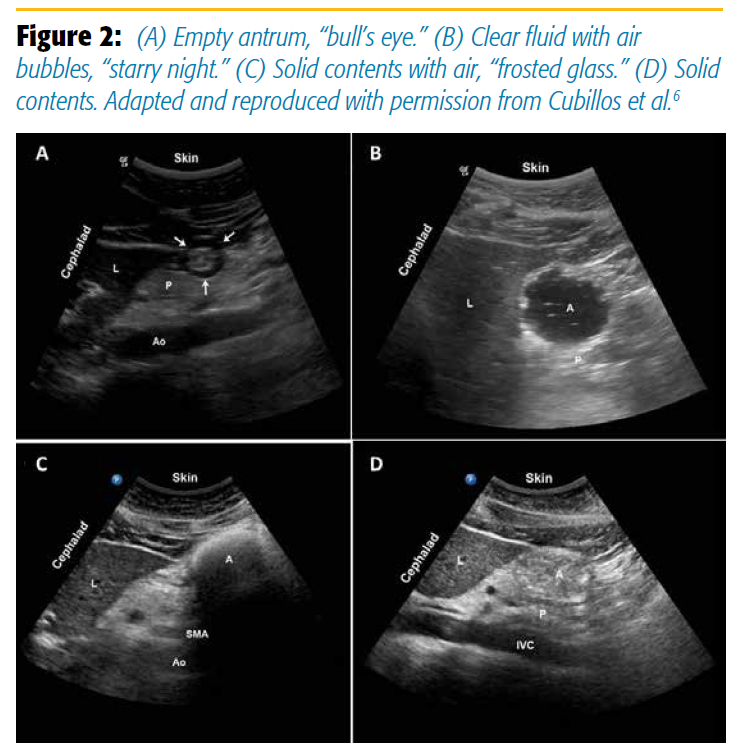

An empty antrum will have contracted, thickened walls, giving it a target or bull’s-eye appearance (Figure 2A). The anterior and posterior walls are juxtaposed against each other. A clear fluid-filled antrum will be distended, with thin walls and homogeneous, hypoechoic content. Air and gas bubbles may be present and appear as mobile punctate echoes, giving the antral lumen a “starry night” appearance (Figure 2B). Solid contents are heterogeneous with a mixed echogenicity (Figure 2D). Air is often entrained with a food bolus during chewing and swallowing. The air-solid mixture creates artifacts that may obscure the posterior wall. This is called the frosted-glass sign (Figure 2C) and is associated with a recent solid meal.